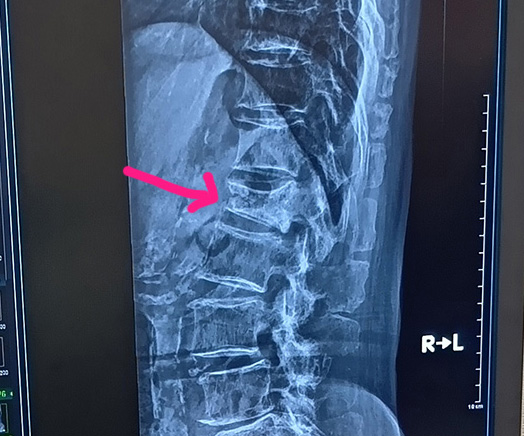

これが先週のレントゲン

矢印のところ見て

ちょうど3か月たって ようやく治ってきた実感がわきました~♪

でもまだ危ないのでコルセットはつけてるけどねw

12月まではやってたほうがいいってお医者さんに言われたし~